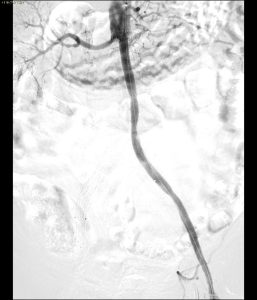

- Ricanalizzazione con filo guida

- Predilatazione

- Stenting

- By pass chirugico